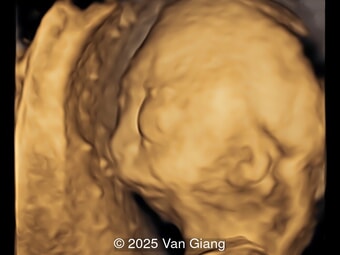

A 35-year-old secundigravida was referred to our unit at 20 weeks gestation for evaluation of suspected fetal skeletal abnormalities. Her first child was healthy, and her personal and family history were otherwise unremarkable. Two years later in a subsequent pregnancy, the patient presented for ultrasound evaluation. This examination was performed at 13 weeks of gestation and demonstrated the following findings: